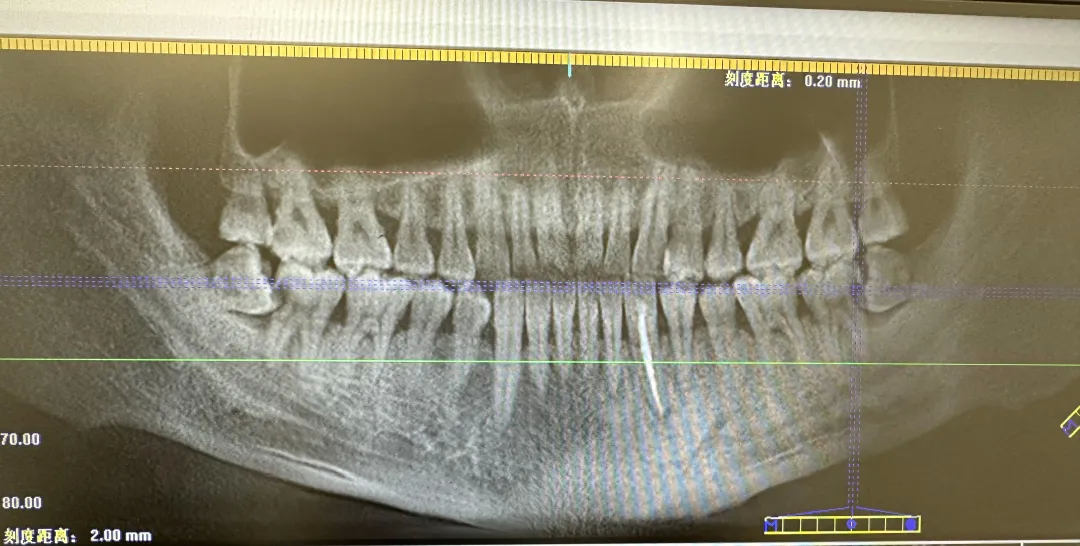

您下面智齿斜着长的,跟前面的第二磨牙经常性食物嵌塞,把第二磨牙的邻面蛀坏了,拍个片子看看吧。

您两边的智齿都把前面的第二磨牙顶坏了,治疗计划是拔除智齿,治疗第二磨牙,要来好几次了,费用也不低。